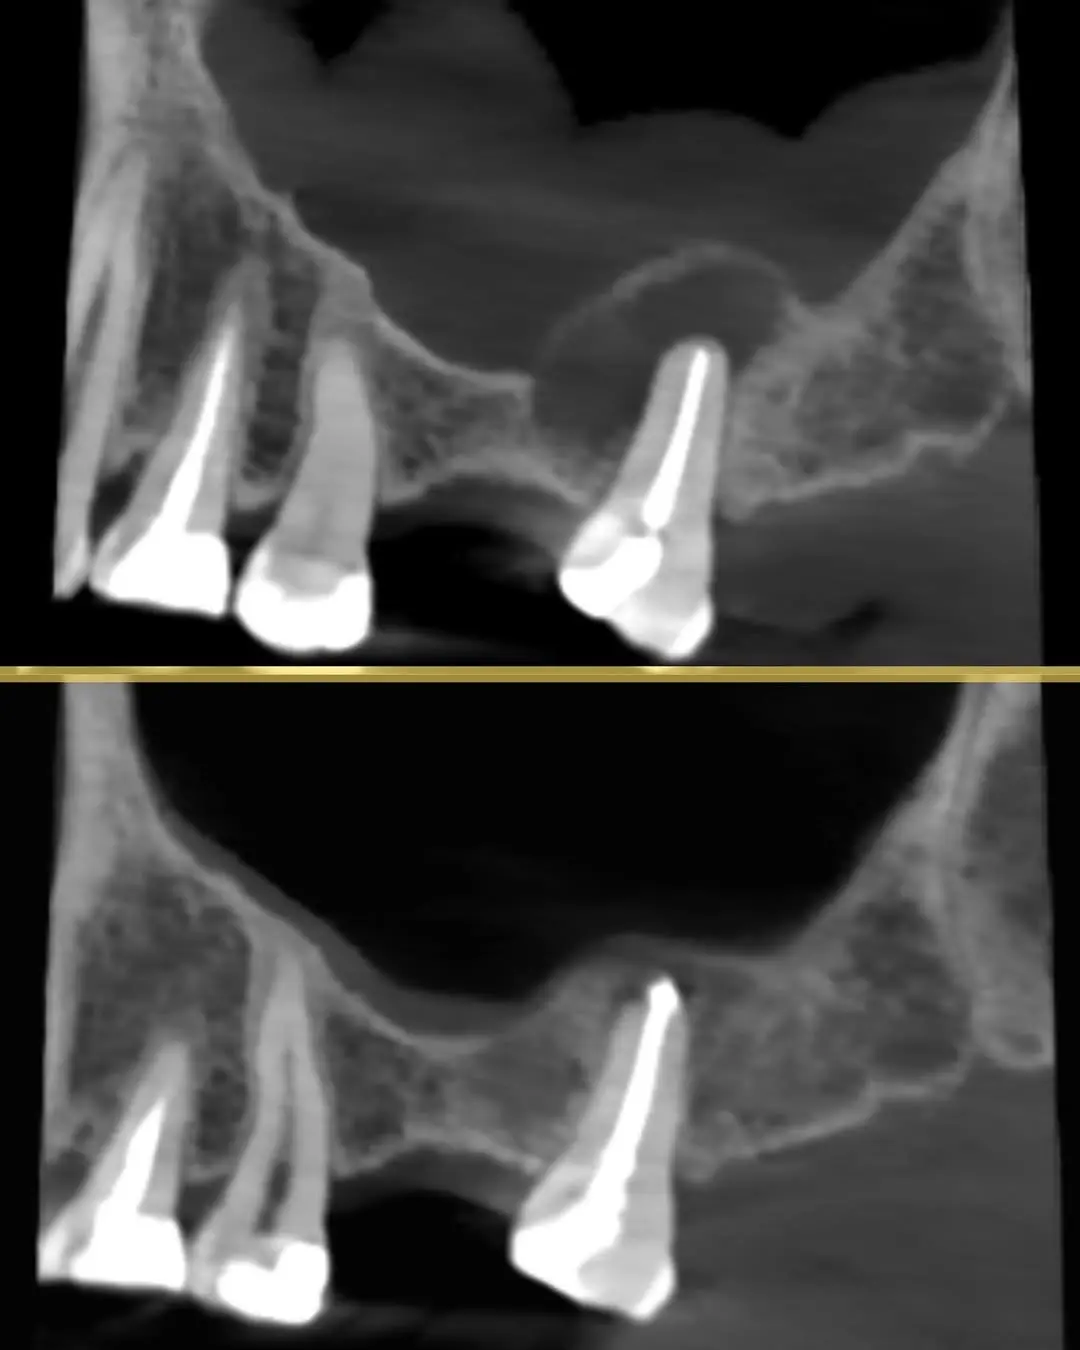

يقود رحلة علاج الجذور داخل مركبة كلاس بخبرة ودقة عالية مع تركيز على إنقاذ الأسنان الطبيعية كلما كان ذلك ممكناً. يمتلك أكثر من 10 سنوات خبرة سريرية ومخصص في حالات حشوات الجذور المعقدة وكذلك مشاكل تآكل العظم. يعتمد على التشخيص المتقدم والتقنيات الحديثة للوصول إلى أدق تفاصيل الجذور ومعالجتها بكفاءة عالية مع ضمان تجربة علاج مريحة وأمنة للمريض ومتابعة دقيقة للحصول على أفضل النتائج واستعادة الراحة والوظيفة الطبيعية للأسنان. بالإضافة إلى خبرته العملية هو متحدث دولي في مجال علاج الجذور ومتحدث رسمي لشركات عالمية مرموقة مثل Woodpecker وOrikam وMDcluss، ما يعكس مستوى عالمي من المهارة والمعرفة التي يقدمها في كل عالج.

نتائج حالات د. اثير عدنان